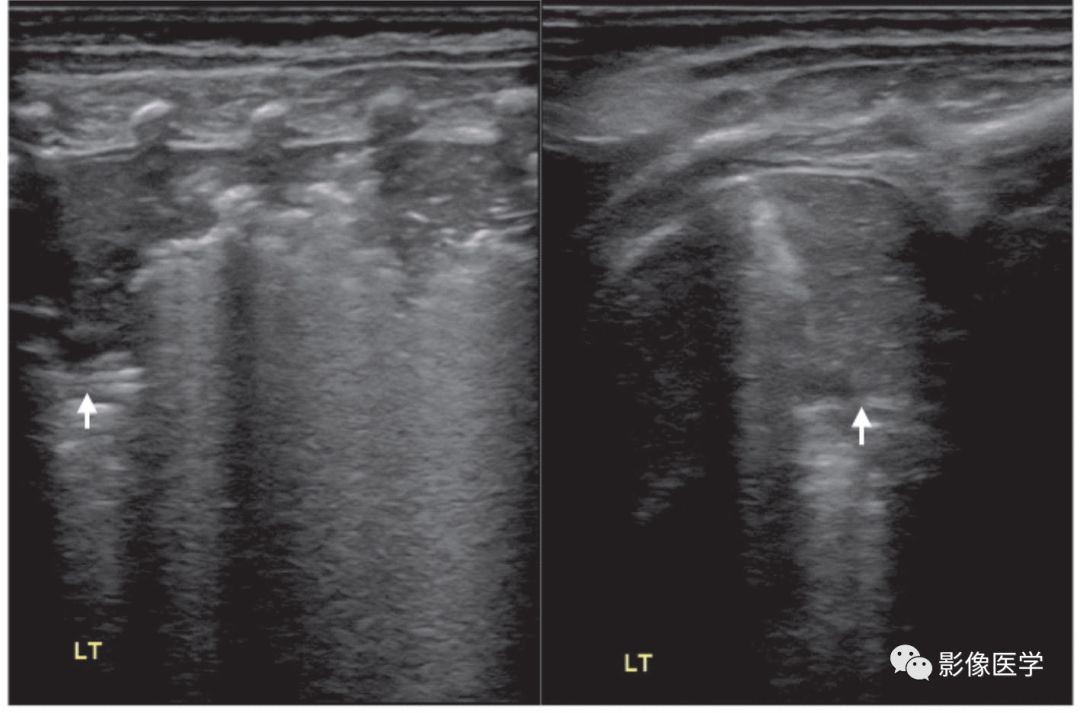

图6-13 呼吸机相关性肺炎(5)

患儿,男,胎龄37周,剖宫产分娩。因呼吸困难入院,肺脏超声呈RDS改变[因宫内感染(WBC 28.8×109/L,N 86%,杆状核粒细胞比例17%,CRP 24mg/L,PCT 85ng/mL)继发RDS],给予呼吸机治疗。出生后第5天,肺脏超声显示左肺(左:探头与肋骨垂直扫描)、右肺(右:探头与肋骨平行扫描)各见累及1个肋间的肺实变(箭头所示),左肺可见支气管充气征;右肺实变程度较深,支气管内充气已被全部吸收,呈低回声实变区。